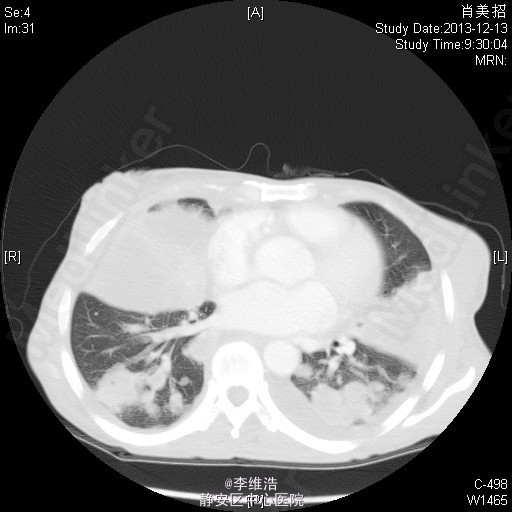

患者,女,53岁。因“咳嗽、咳痰、发热2月余”入院。 2月余前出现右耳听力下降,流脓,后出现咳嗽、咳白痰和脓性痰,伴盗汗、发热、咯血。1月前出现腹胀明显,纳差,双下肢水肿。曾予各种抗菌素治疗,无明显效果。

T38.8 ℃,P118 次/分,R20次/分,BP132 /71 mmHg。精神差,慢性病容,面色苍白,双侧颈部及锁骨上可触及数个黄豆小大淋巴结,无压痛,两肺呼吸音粗,可闻及少量湿性啰音,双下肺呼吸音消失。心界不大,心率118次/分,律齐。腹膨隆,可见胃型,上腹硬,有压痛,肝脾肋下未及,肝肾区无叩击痛,双下肢凹陷性水肿。 胸部CT:两肺多发占位,纵膈淋巴结肿大,双侧少量胸腔积液。 左侧颈部淋巴结穿刺:淋巴结反应性增生。 经皮肺穿刺:肉芽肿性炎伴微脓肿形成,并片状坏死。